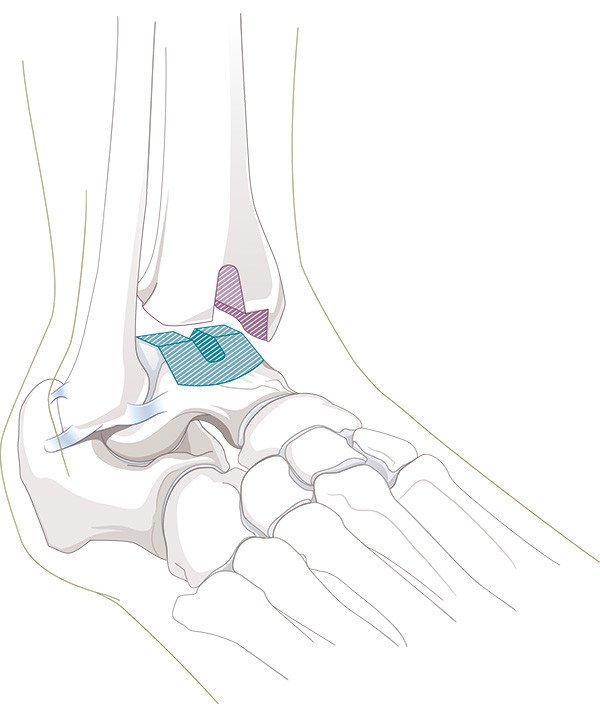

Kunstgelenk

Zur Behandlung der Arthrose an grossen Gelenken wie Hüfte, Knie, Schulter oder Ellbogen hat sich der Gelenkersatz seit Jahrzehnten etabliert. Weil es funktionell zu den grossen Gelenken zählt, wurde schon früh versucht, auch im Sprunggelenk Kunstgelenke einzusetzen. Verschiedene Gründe haben aber noch bis Mitte der 70er-Jahre fast konstant zum Versagen dieser Kunstgelenke geführt. Neuere Designüberlegungen haben schliesslich die Weiterentwicklung der Sprunggelenkprothese hervorgebracht, wie wir sie heute kennen.